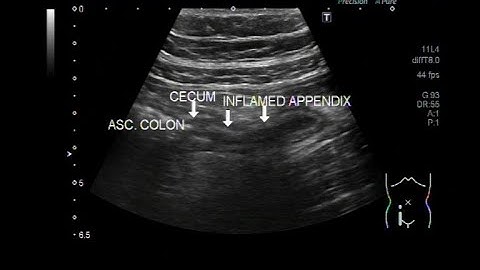

Ultrasound video showing inflamed gangrenous appendix, intramural gas shadows in base of appendix